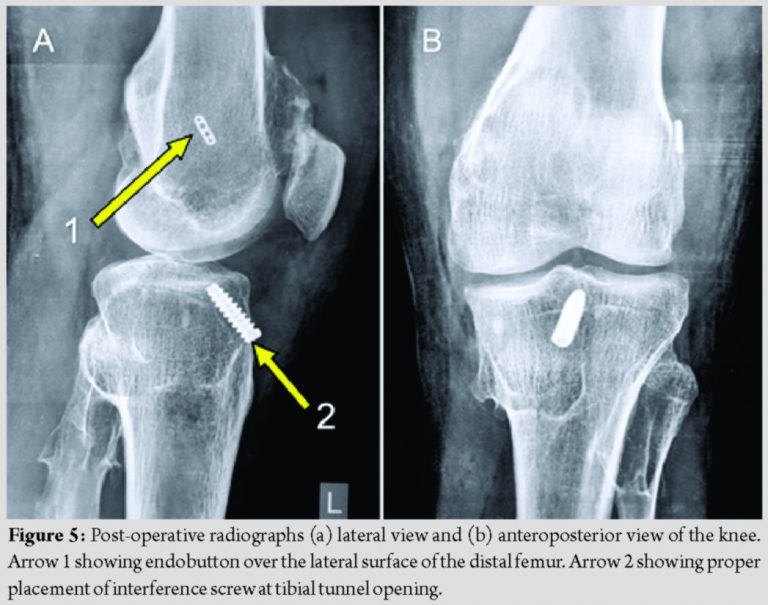

The problem faced by us was in graft harvesting. The tibial osteochondroma was underlying the pes insertion. There was difficulty in the identification of pes. A vertical 2.5 cm incision was taken for a better orientation of pes tendons. The upper border of pes insertion was then identified, which was lying caudal to the medial tibial osteochondroma. Pes insertion was cut vertically, and semitendinosus, and gracilis tendons where caught in a Kocher’s forceps. Tendons were freed from the fascial bands. It was difficult to maneuver the tendon stripper around the tumor. Finally, the stripper was passed to cross the tibial osteochondroma and retrieve the graft. Reaming for the tibial interference screw passed through the junction of the tumor and normal bone. The purchase of the interference screw in the bone, however, was firm. Post-fixation probing of the graft revealed an adequately tensioned graft. Gentle, on table anterior drawer testing revealed correction of pre-operative status. There was no impingement of the graft in the femoral notch on full extension. Post-operative radiographs revealed the proper placement of interference screw at the tibial tunnel opening and endobutton over the lateral surface of the distal femur (Fig. 5).